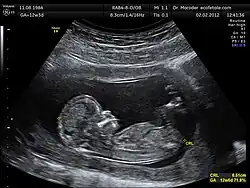

Gängige Methoden sind zum einen die nicht-invasiven, nur von außerhalb des Körpers vorgenommenen Untersuchungen wie die Ultraschalluntersuchung (Sonographie), zu der die Nackentransparenzmessung, die Nasenbeinmessung (in der 12. bis 14. Schwangerschaftswoche), die Fetometrie, der Feinultraschall, die Doppler-Sonographie, der 3D-Ultraschall und der 4D-Ultraschall gehört. Auch die Untersuchungen von Hormonkonzentrationen im mütterlichen Blut (serologische Untersuchungen) wie beispielsweise der Triple-Test, der Quadruple-Test und als Kombination beider Methoden das Erst-Trimester-Screening (ETS, eine Untersuchung im ersten Schwangerschaftsdrittel) und das integrierte Screening (kombinierte Untersuchung der biochemischen Serum-Parameter zur Risikoermittlung für fetale Chromosomen- und Verschlussstörungen) gehören zu den nicht-invasiven Methoden. Ebenso zu der nichtinvasiven Diagnostik zählt der bereits ab der 9. Schwangerschaftswoche mögliche pränatale Vaterschaftstest, bei dem fetale DNA anhand einer Blutprobe der Mutter isoliert und analysiert wird. Invasive, das heißt innerhalb des Körpers vorgenommene Untersuchungen der Pränataldiagnostik sind die Chorionzottenbiopsie (CVS), die Amniozentese (AC) und die Nabelschnurpunktion. Eine frühere Methode der Pränataldiagnostik war die Amnioskopie.

Erste Amniozentesen zur Pränataldiagnostik wurden 1930 von Thomas Menees und anderen[1] durchgeführt.[2] Die Grundlage moderner pränataler Diagnostik legte der britische Geburtshelfer Ian Donald 1958 mit der erstmaligen sonographischen Darstellung eines ungeborenen Kindes.[3][4] Die technische Weiterentwicklung der Ultraschallgeräte ermöglichte eine hohe Detailauflösung und damit die Erkennung von strukturellen Fehlbildungen fetaler Organe mit hoher diagnostischer Sicherheit. So wurden die Diagnose von Bauchwanddurchbrüchen, Zwerchfellhernien, Verlagerungen der Herzachse, Fehlbildung von Organen wie z. B. der Lunge oder der Nieren, Zystennieren, Fehlbildungen der Extremitäten, Obstruktionen im Magen-Darm-Trakt etc. möglich.